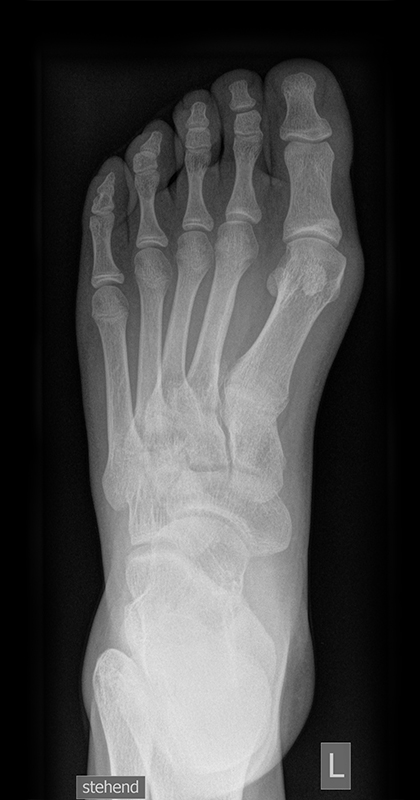

Die folgenden Bilder zeigen die belastete Röntgenaufnahmen des linken Fußes einer jungen Patientin zu Beginn der Therapie und nach 6 Monaten Training. Erkennbar ist die höhere muskuläre Verspannung des Fußes mit verbesserter Stellung der milden Hallux valgus Deformität.